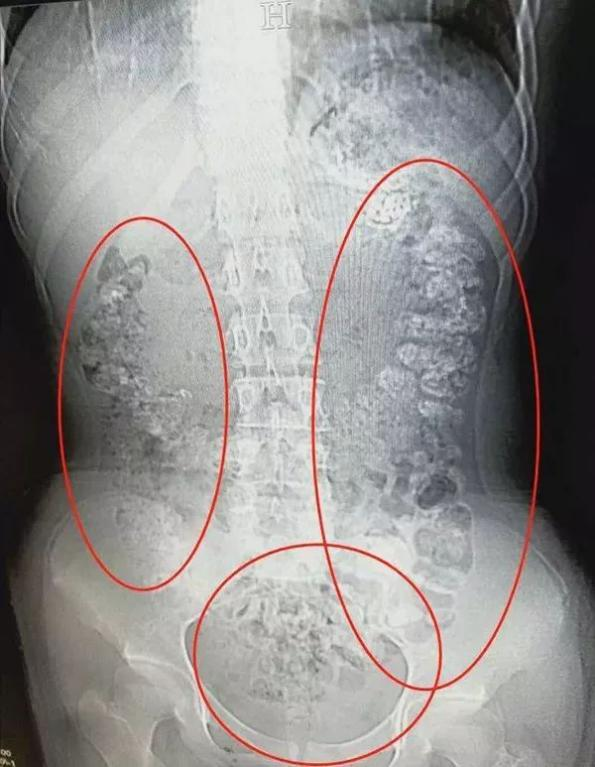

之前就有14岁女孩喝了珍珠奶茶后5天没有排便,还肚子疼,最后CT检查发现胃肠道布满一颗颗没有消化的“珍珠。

医生就表示,珍珠奶茶里的“珍珠”是木薯淀粉制成,本身就不易消化,有的商家为提升口感还会加入增稠剂等添加剂,大量连续食用,胃肠功能紊乱都是轻的。